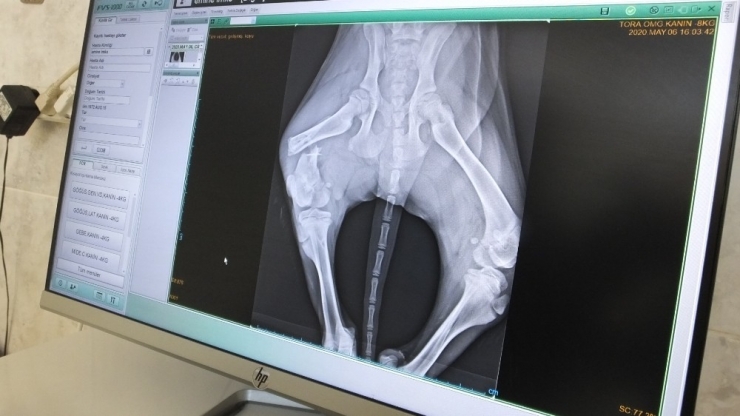

Burhaniye ilçesinde, bir otomobilin çarptığı yavru sokak köpeğine veteriner hekim Hakan Kol sahip çıktı. Hayvanın röntgenini çeken Kol, arka bacakta kırık belirlerken, yavru köpeğin kırık bacağına operasyon yaptı.

Enver Güreli Caddesi'nde yavru köpeğe otomobil çarparken, bacağı kırılan hayvan kıvranmaya başladı. Hayvanın yaralandığını gören duyarlı vatandaşlar veteriner hekim Hakan Kol'u aradı. Dakikalar içinde kaza yerine gelen araç yavru köpeği kliniğe götürdü. Köpeği muayene eden Kol, çektiği röntgen sonucu hayvanın sağ bacağında kırık belirledi. Hayvanın bacağına operasyon yapan Kol, iyileşeceğini anlatırken sürücüleri daha dikkatli olmaya çağırdı. Köpeği tedaviye alan veteriner hekim Hakan Kol, "Gelen ihbar üzerine yavru köpeğe arabanın çarptığını öğrendik. Gidip hayvanı aldık. Travma var. Arka bacakta femurda kırık var çektiğimiz röntgen sonucuna göre. Operasyona alacağız. Daha iyi olacak inşallah. Yalnız sürücülerin daha duyarlı olmalarını ve daha yavaş gitmelerini rica ediyorum" dedi.